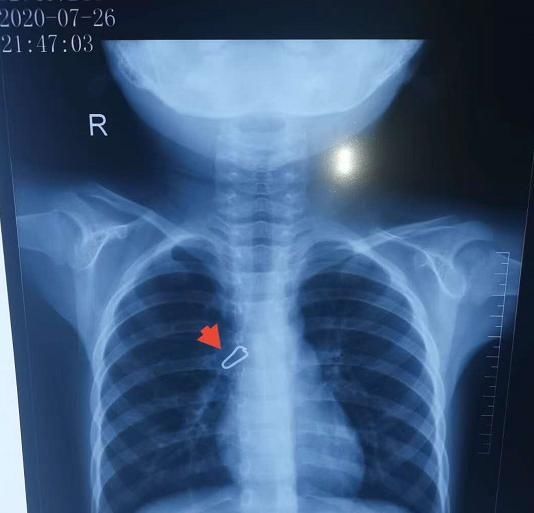

据主治医生王琦介绍,小钦溪在凌晨被送到医院时,出现 " 异物卡喉 " 的感觉已经有四个小时时间了,通过胸部 CT 医生们发现,在小钦溪的右胸气管内有个类似于 " 金属扣 " 一样的东西。

因为没有办法判断它这个金属的东西在里面会不会对女童气道产生什么危害或影响,如果它比较尖锐,就很可能划破气道,如果这个金属的东西上面会有一些腐蚀性的东西或者化学性的东西,也会对气道都会有影响。所以,医生决定立即手术。当天凌晨,在电子支气管镜的帮助下,医护人员顺利将这个 " 金属扣 " 取出,帮助孩子成功脱离险境。